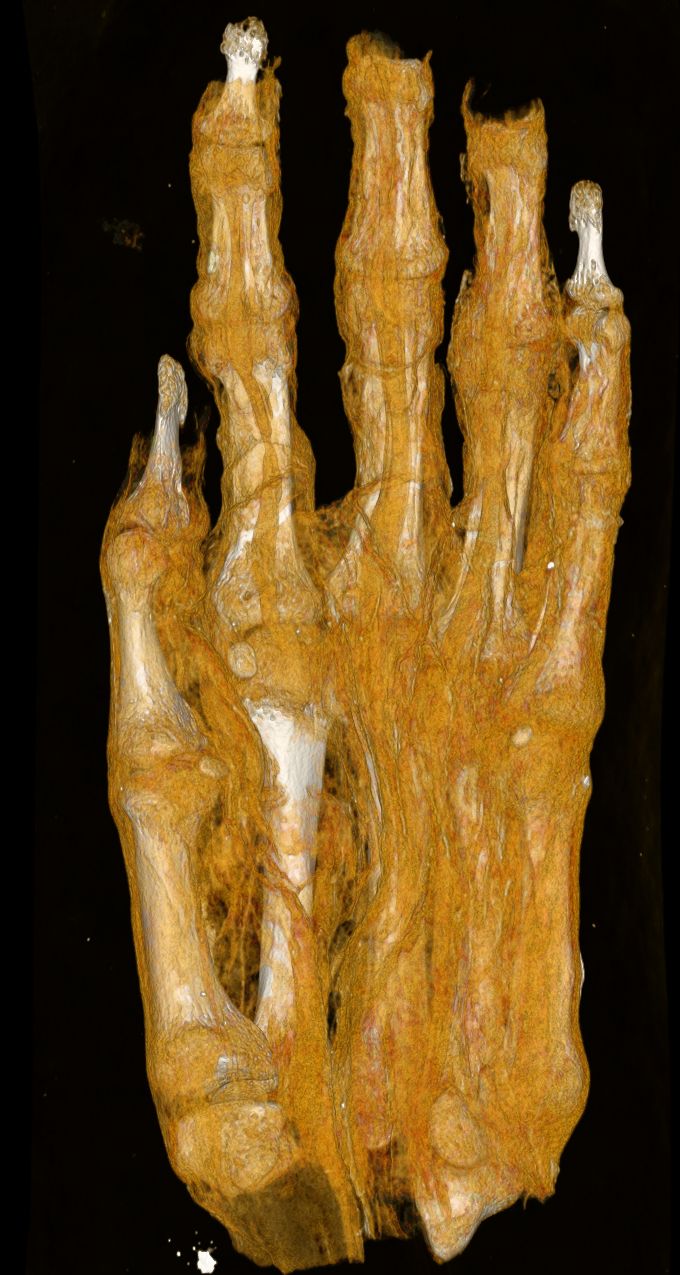

The examination of a set of remains – previously interpreted merely as a mummy bundle – yielded particularly noteworthy results. When the find arrived at the museum, in the absence of imaging tests, it was initially identified as a human head and later, possibly, as a bird mummy. However, a previous CT scan clearly showed that the find is, in fact, an adult foot. The current imaging analysis aims to determine the extent to which the textile remnants can provide insight into the mummification technique, the age of the mummified individual, and any illnesses the individual may have had. The current images clearly reveal the different layers of the bandage and show their different structural characteristics. These findings may lay the groundwork for further historical and technological investigations. The remains were presumably part of a complete mummy, but the reason and time of the dissection are currently unknown.

The analysis of the mummified hand included in the study can also offer valuable information. Based on the size, development, and morphological characteristics of the bones, researchers aim to determine whether the remains belonged to a child or an adult. They may also be able to estimate the individual’s sex and age.